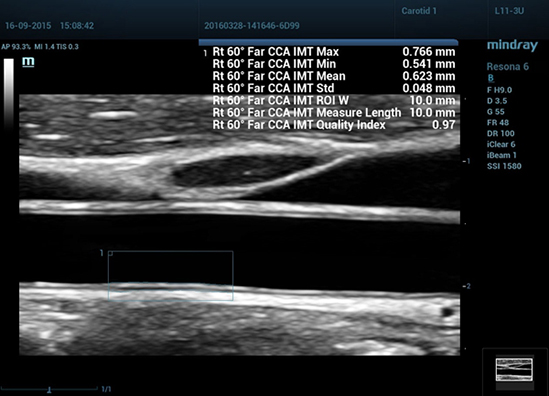

RIMT (RF-Data IMT вАФ –Є–Ј–Љ–µ—А–µ–љ–Є–µ —В–Њ–ї—Й–Є–љ—Л –Ї–Њ–Љ–њ–ї–µ–Ї—Б–∞ –Є–љ—В–Є–Љ–∞-–Љ–µ–і–Є–∞ —Б –њ–Њ–Љ–Њ—Й—М—О –і–∞–љ–љ—Л—Е –Є–Ј —А–∞–і–Є–Њ–і–Є–∞–њ–∞–Ј–Њ–љ–∞)

–Ч–∞ —Б—З–µ—В —Б–Њ–і–µ—А–ґ–∞—Й–Є—Е—Б—П –≤ –љ–µ–Њ–±—А–∞–±–Њ—В–∞–љ–љ–Њ–Љ –∞–Ї—Г—Б—В–Є—З–µ—Б–Ї–Њ–Љ —Б–Є–≥–љ–∞–ї–µ –і–∞–љ–љ—Л—Е –Є–Ј —А–∞–і–Є–Њ–і–Є–∞–њ–∞–Ј–Њ–љ–∞ (RF-Data), —В–µ—Е–љ–Њ–ї–Њ–≥–Є—П RIMT –Њ–±–µ—Б–њ–µ—З–Є–≤–∞–µ—В –∞–≤—В–Њ–Љ–∞—В–Є—З–µ—Б–Ї–Њ–µ –Є–Ј–Љ–µ—А–µ–љ–Є–µ —В–Њ–ї—Й–Є–љ—Л –Ъ–Ш–Ь –≤ —А–µ–ґ–Є–Љ–µ —А–µ–∞–ї—М–љ–Њ–≥–Њ –≤—А–µ–Љ–µ–љ–Є —Б –Є—Б–Ї–ї—О—З–Є—В–µ–ї—М–љ–Њ –≤—Л—Б–Њ–Ї–Њ–є —В–Њ—З–љ–Њ—Б—В—М—О –і–Њ 5 –Љ–Ї–Љ, —Б –Ї–Њ–ї–Є—З–µ—Б—В–≤–µ–љ–љ—Л–Љ –∞–љ–∞–ї–Є–Ј–Њ–Љ –≤ –њ—А–µ–і–µ–ї–∞—Е 6 —Б–µ—А–і–µ—З–љ—Л—Е —Ж–Є–Ї–ї–Њ–≤ –Є —Б –Љ–µ–љ—М—И–µ–є –Ј–∞–≤–Є—Б–Є–Љ–Њ—Б—В—М—О –Њ—В –Ї–∞—З–µ—Б—В–≤–∞ –Є–Ј–Њ–±—А–∞–ґ–µ–љ–Є—П вАУ –≤—Б–µ —Н—В–Њ –Ј–љ–∞—З–Є—В–µ–ї—М–љ–Њ –њ–Њ–≤—Л—И–∞–µ—В —В–Њ—З–љ–Њ—Б—В—М –і–Є–∞–≥–љ–Њ—Б—В–Є–Ї–Є.